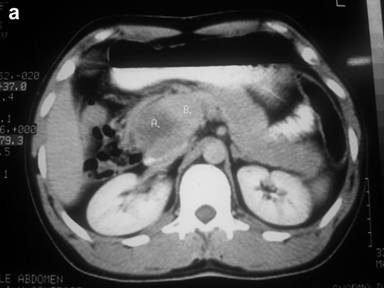

A thirty-year-old man presented with the chief complaint of mass in the right upper abdomen since one and half year. It was gradually increasing in size and was associated with occasional upper abdominal pain. Pain was dull in nature, non-radiating with no specific aggravating and relieving factor. There was history of incomplete bowel evacuation sensation and increased frequency of defecation. There was no history of vomiting, gastrointestinal bleed, jaundice, anorexia and weight loss. On physical examination, there was no pallor, jaundice and lymphadenopathy. A large firm mass about 15x10 cm extending into epigastrium, umbilical and right hypochondrium on per abdomen examination. It had round shape, bosselated surface, smooth margins, and was mobile in the transverse direction. There was no abnormality on digital rectal examination and proctoscopy. Routine laboratory tests were within normal limits. Ultrasound abdomen showed 15x10 cm heterogeneous mass in the umbilical region displacing the adjoining gut loops with no invasion. CECT abdomen showed 15x10 cm size, well defined mass with heterogeneous density in the retroperitoneum extending from pancreas to pelvic brim. It had enhancing peripheral component and non-enhancing (necrotic) central component (Figure 1). Fine needle aspiration cytology of mass smear showed blood only. On exploratory laparotomy there was large hyper vascular mass protruding through the transverse colon mesentery. Mass appeared to be originating from the anterior surface of head of pancreas. It was attached to the whole length of anterior surface of pancreas and macroscopically was not attached with the duodenum except for about one or two cm near the lower end of second part of duodenum (Figure 2). There was no metastasis in liver or peritoneum. Pancreaticoduodenectomy was done. Histopathology showed spindle cell tumor with palisading pattern and foci of necrosis (Figure 3). The mitotic count was up to 15/50 HPF. Tumor was involving duodenal muscularis propria with no infiltration in the duodenal epithelial layer and the pancreas (Figure 4). Immunohistochemical study revealed positive staining for CD117, CD34, vimentin, smooth muscle actin, and negative staining for desmin and CD31 (Figure 5). Based on these findings, the tumor was finally diagnosed as gastrointestinal stromal tumor (GIST) arising from the duodenal wall, growing exophytically and attached with the pancreas without infiltrating the pancreas. Post-operatively patient had biliary leak which was managed conservatively and discharged in satisfactory condition with the advice to take imatinib 400 mg daily.

Figure 1. Contrast enhanced computed tomography showing: a. heterogeneous mass arising from pancreas; b. A 15x10 cm heterogeneous mass with peripheral enhancement and central necrosis. |